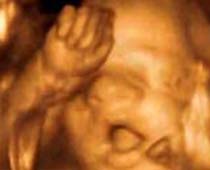

- 3D Photos échographie du comportement du fœtus

- Le comportement du fœtus pendant la grossesse

- Commencer l'album photo de votre bébé